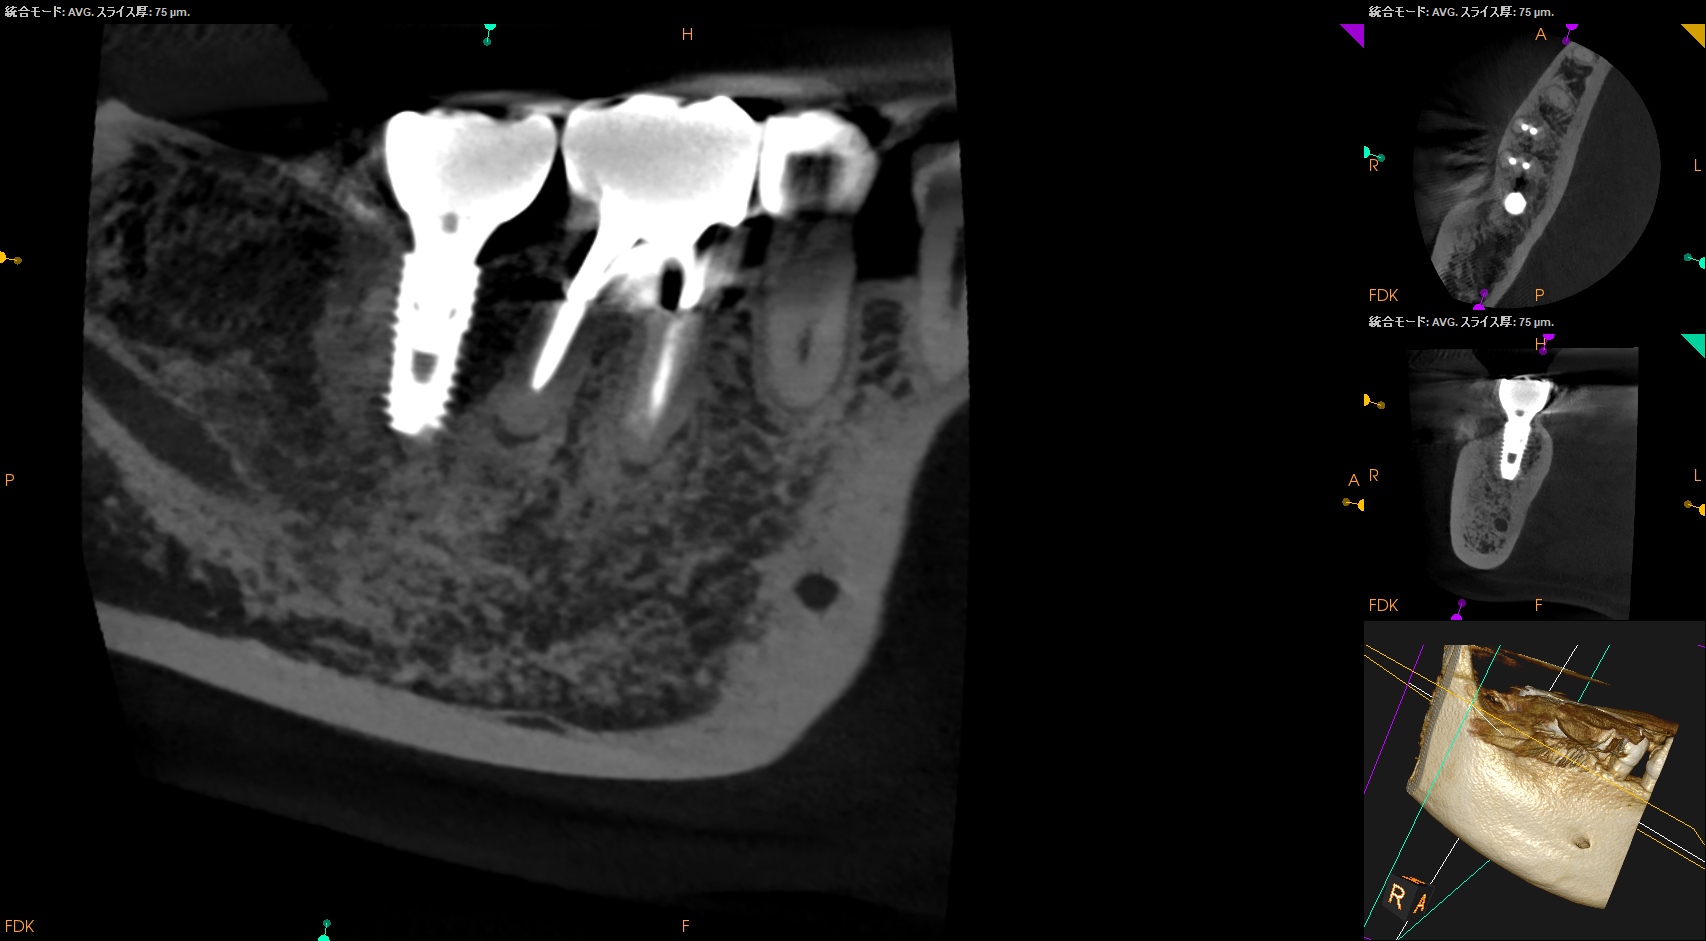

CBCT(2025.10.27)

MのApexに到達するにはCEJよりも12.5mm下方の歯槽骨を2mm削合(Osteotomy)しなければならない。

Apexを見つけたら3mm切断するがこの時の頬舌的な幅径が6.3mmだ。

リンデマンバーの半分よりも長い。

またDはApexに到達するには、CEJよりも13mm下方の歯槽骨を3mm削合する必要がある。

まさに…芋掘りだ。。。

クラウンのマージン部よりも13mm下方にDのApexがある。

そこに行き着くには歯槽骨を3mm削合する必要がある。

術後にPA, CBCTを撮影した。

気泡はあるが問題はないとして縫合した。